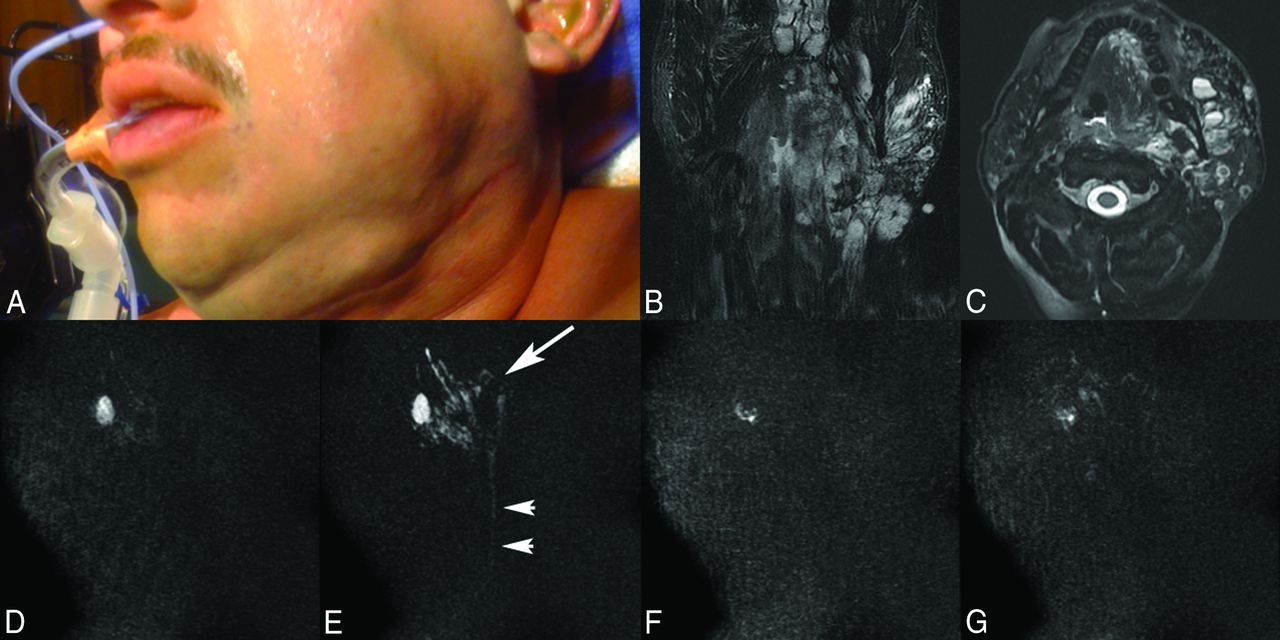

A 36-year-old man with a left facial venous malformation who undergone 14 treatments during the past 3 years, the last 2 with MR imaging guidance. Overview of the direct-injection MR angiography technique for embolization of the lesion. A, Patient photograph before MR sclerotherapy shows left facial swelling from a persistent left facial venous malformation. Coronal (B) and axial (C) T2-weighted fat-saturated MR images demonstrate the typical imaging characteristics of a venous vascular malformation, including a mixed signal intensity but mostly bright trans-spatial lesion extending both superficial and deep to the left mandible composed of multiloculated blood-filled channels with fluid-fluid levels producing local mass effect. Pretreatment MR angiograms, early (D) and late (E) phase, show appropriate needle positioning within the loculated blood-filled channels of the venous malformation (arrow) with slow venous runoff into a small draining vein (arrowheads). Posttreatment MR angiograms, early (F) and late (G) phase, demonstrate pruning of the vascular channels of the venous malformation with markedly diminished flow into the draining vein, compatible with satisfactory embolization of the lesion.